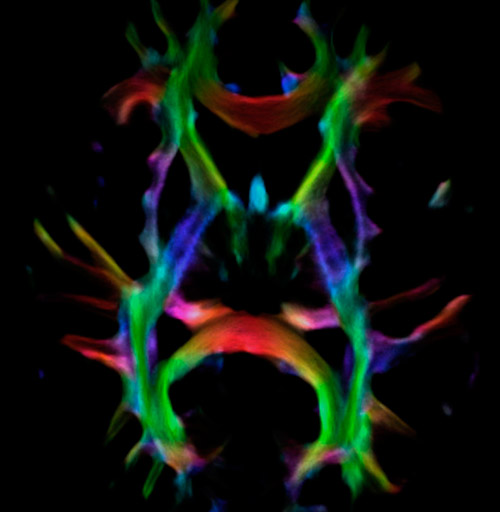

DEC TDI

UVM research fiber tracking density

Super-resolution directionally encoded color track-density imaging overlaid on T1-weighted structural MRI.

Super-resolution directionally encoded color track-density imaging

UVM research fiber super resolution

UVM research fiber tracking

UVM research super resolution